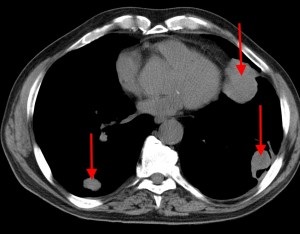

Stânga - cancer renal cu metastaze la plămâni, prognosticul în acest caz este nefavorabil din cauza efuziuni pleurale metastatice și insuficiență respiratorie. buzunare definite pe ambele părți. Dreapta - mici si sredneochagovaya difuzarea de cancer la ficat.

Hematogenă mai multe noduri secundare în cancerul renal, tomografie computerizata (CT).